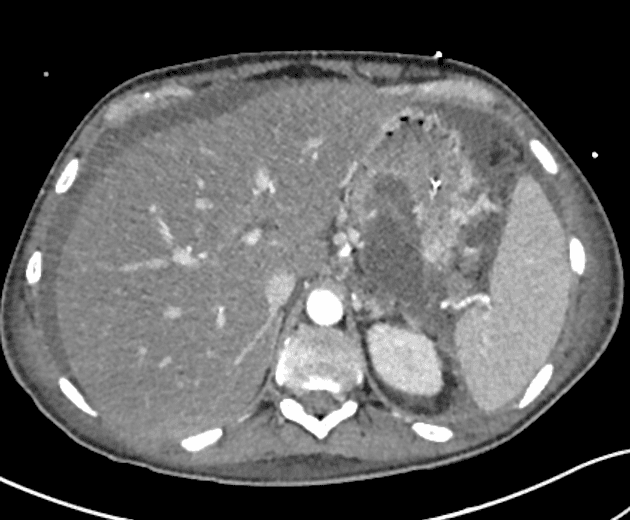

Axial C+ portal venous phase

- Tụy phì đại lan tỏa và tăng quang đồng nhất, phù hợp với viêm tụy phù nề giao kẽ cấp tính (acute interstitial edematous pancreatitis), đi kèm theo là các ổ dịch quanh tụy (peripancreatic fluid collections).

- Huyết khối tĩnh mạch lách (splenic vein thrombosis) thứ phát do viêm lân cận.

- Giá trị suy giảm ở gan thấp hơn lách, gợi ý gan nhiễm mỡ (fatty liver).

Các ổ dịch quanh tụy cấp tính (acute peripancreatic fluid collections)

Các ổ dịch quanh tụy cấp tính (APFCs) là phát hiện hình ảnh phổ biến trong viêm tụy phù nề giao kẽ cấp tính. Theo Phân loại Atlanta sửa đổi, APFCs được định nghĩa là các ổ dịch đồng nhất, có mật độ dịch ở vùng quanh tụy, xuất hiện trong vòng 4 tuần đầu tiên kể từ khi khởi phát triệu chứng và không chứa thành phần hoại tử rắn. Những ổ dịch này thường tự hồi phục với điều trị bảo tồn. Ngược lại, nếu có mô hoại tử, thuật ngữ 'ổ hoại tử cấp tính' được sử dụng. Sau bốn tuần, nếu ổ dịch hình thành vách bao, nó được phân loại lại là nang giả nếu không có hoại tử, hoặc ổ hoại tử có vách (WON) nếu vẫn còn mô hoại tử. Huyết khối tĩnh mạch lách là biến chứng mạch máu khu trú của viêm tụy cấp, thường thứ phát do thay đổi viêm ở các mô quanh tụy. Mặc dù chống đông hệ thống có thể được cân nhắc trong một số trường hợp, điều trị chủ yếu tập trung vào xử lý viêm tụy nền.